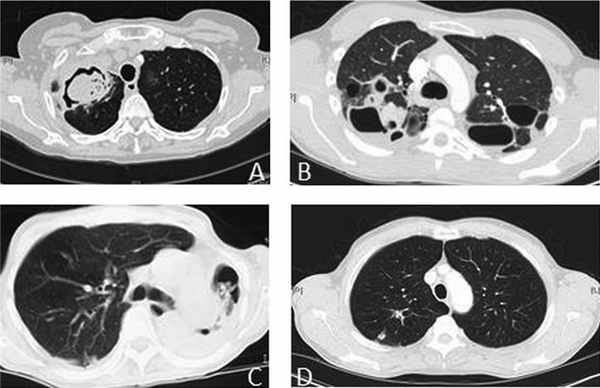

КТ больных с различными формами хронического аспергиллеза легких. (А) Простая аспергиллома; (B) Хронический полостной аспергиллез легких; (C) Хронический фиброзирующий аспергиллез легких; (D) Аспергиллезный узелок. Рисунок взят из Kosmidis C, Denning DW, Клинический спектр легочного аспергиллеза, торакс 2015;70:270-277